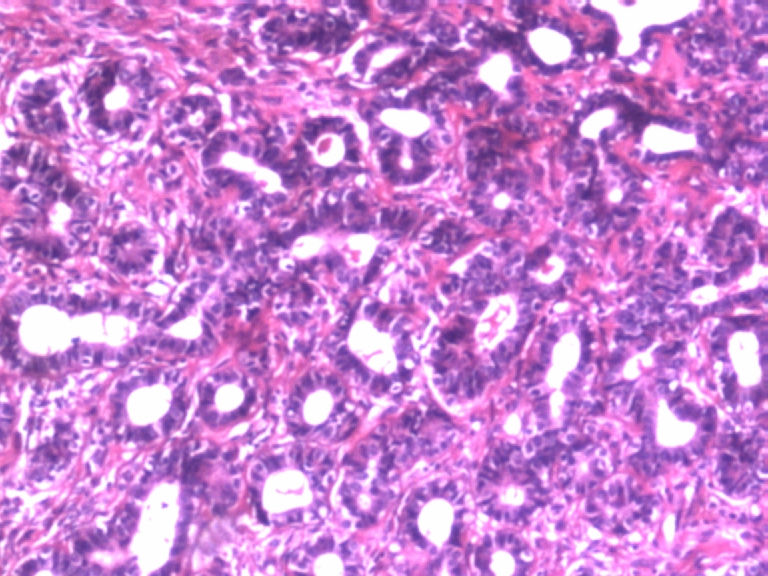

• 乳腺肿物图1

图1

患者,女,29岁,右侧乳腺肿物一个月。切面淡黄,均匀一致,质中。

标签:乳腺管状腺瘤

病变组织小叶结构未见,见管状、盲管状的腺管,周围似有空亮的肌上皮,腺上皮可见细小的核仁,染色质均细,导管上皮普通型增生。有包膜为盲管状腺瘤,则为腺病。

无则为腺病

有肌上皮而且有的地方还有肌上皮增生,应该是腺病,你应该多采些低倍镜的图像,高倍镜的大多了没有太大的意义。